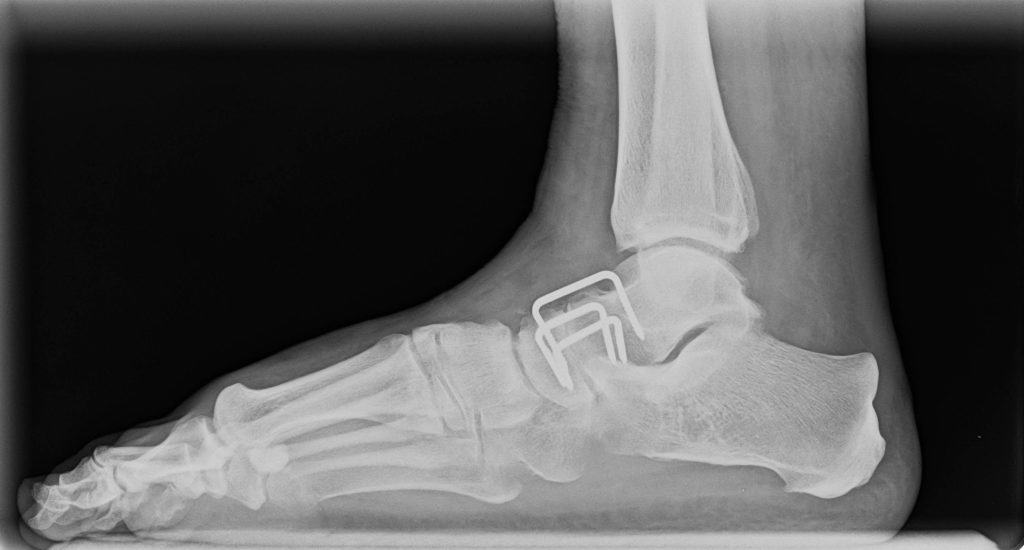

Navedeni zahvat će se najčešće izvoditi iz sljedećih razloga: Kako bi se osobi otklonila bol u zglobu koja ne prestaje, kada je došlo do promjene zgloba i kad on više ne može vršiti svoju funkciju, kada je došlo do slabosti mišića iako je zglob zdrav, kada je došlo do neuspješne artroplastike. Kako se vrši artrodeza? Otklanja se koža, potkožno i masno tkivo, te se otvara zglob uz pomoć rezanja zglobne kapsule. Kirurg će zatim koristiti glodalicu kako bi otklonio svu zglobnu hrskavicu i po potrebi dijelove kosti kako bi čvrsto povezao kosti koje tvore zglob.

Za navedeni postupak se najčešće koriste vijci, metalne ploče, koštani čipovi. Kada su kosti čvrsto povezane, kirurg će zašiti zglobnu kapsulu, potkožno tkivo i kožu. Da li artrodeza donosi rizike? Da. Pacijent može doživjeti stvaranje lažnog zgloba, osjetiti kroničnu bol, imati ograničeno kretanje, senzorne poremećaje, skraćivanje zgloba. Nadalje, mogući su i sljedeći operativni rizici: Ozljeda živca, krvarenje, nastanak modrica, ozljeda okolnog mišića ili tetiva, infekcije, ožiljci, alergijske reakcije.